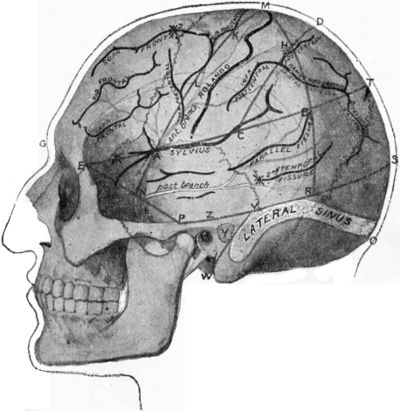

| 179. | Relations of the Motor and Sensory Areas to the Convolutions and to Chiene's Lines | 330 |

| 181. | Chiene's Method of Cerebral Localisation | 336 |

| 186. | Relations of the Middle Meningeal Artery and Lateral Sinus to the Surface as indicated by Chiene's Lines | 353 |